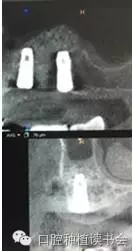

2、經(jīng)側(cè)壁開窗分離粘膜抬高竇底的方法稱為外提升(Lateral Window Technique)。早期由Philip?Boyne提出,后來上頜竇側(cè)壁開窗在粘膜和竇底之間進行骨增量的術(shù)式逐步應(yīng)用開來。側(cè)壁開窗后是否同期植入種植體,根據(jù)RBH,種植體穩(wěn)定性的預判而決定??偟膩碚f,上頜竇外提升術(shù)的成功率86%~100%(Jensen,2009)。根據(jù)CBCT圖像,不但可以提供術(shù)前的種植計劃指導,而且上頜竇外提升術(shù)后的效果,尤其是檢查種植體腭側(cè)是否有植骨不全,都會一目了然。(圖10-12)